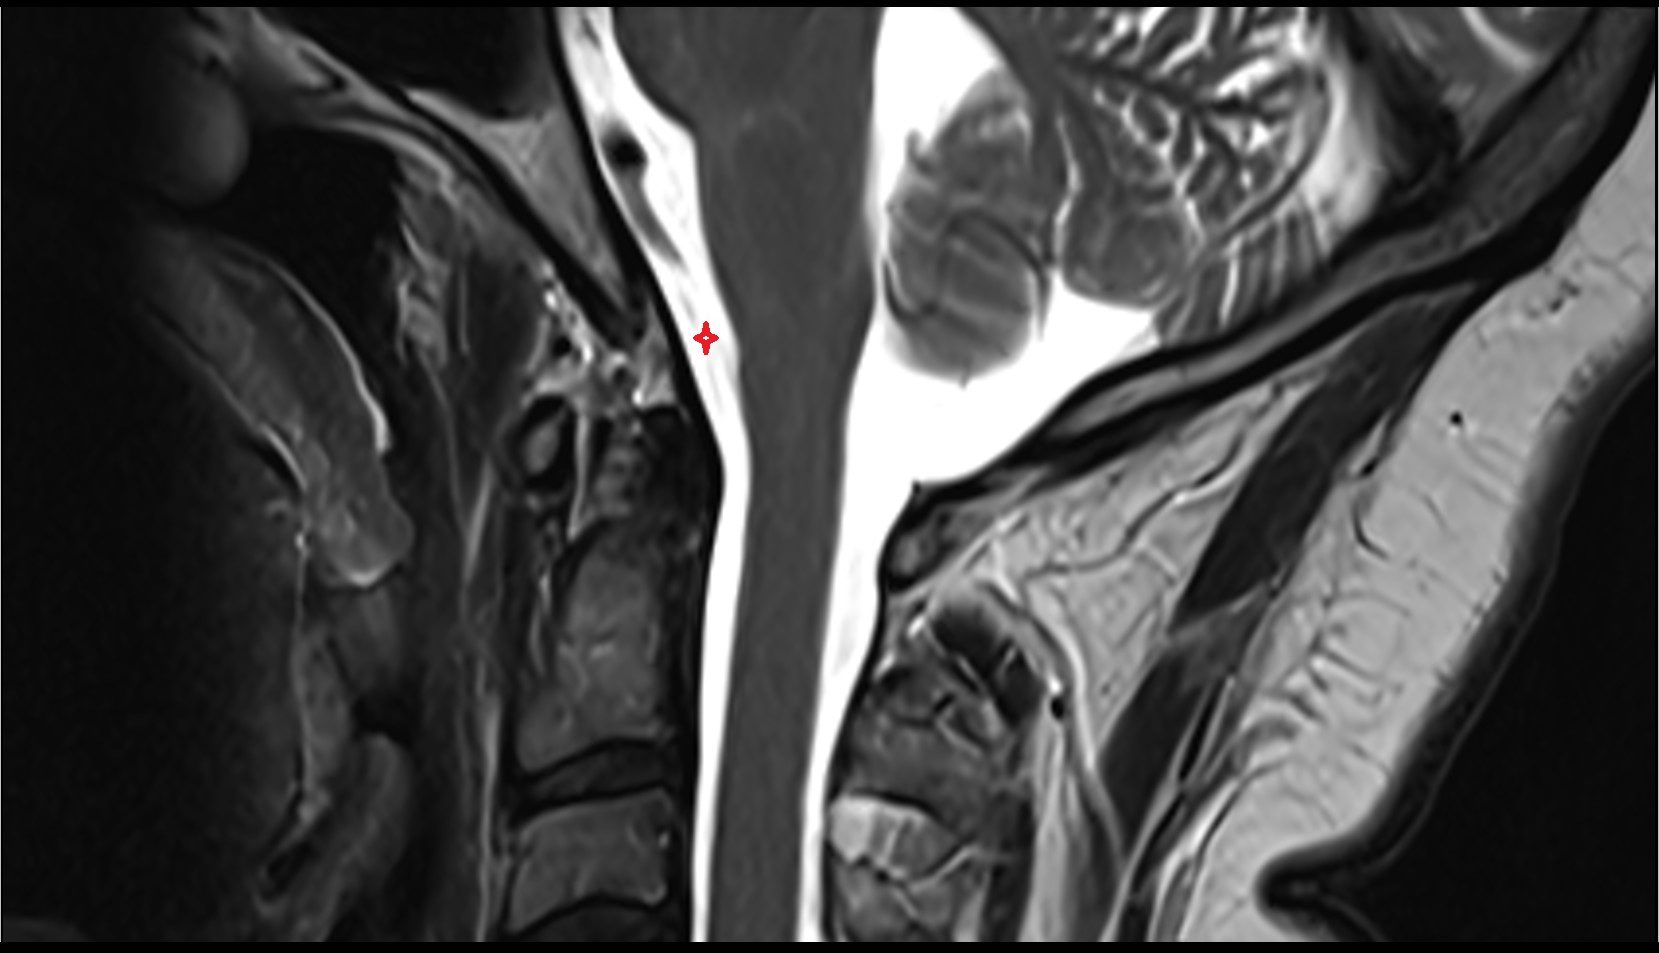

- Upper cervical spinal cord

- Spinal cord